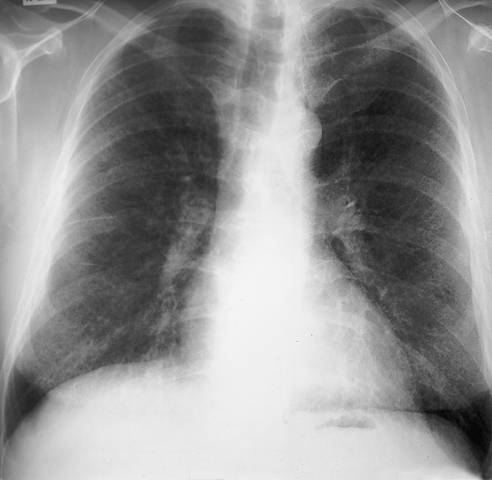

Sarcoidosis in Chest x-Ray

Sarcoidosis in chest x-ray. Chest x-ray shows small disseminated interstitial consolidations. The hilar lymph nodes are not (anymore) enlarged.

Picture: Duodecim Medical Publications Ltd